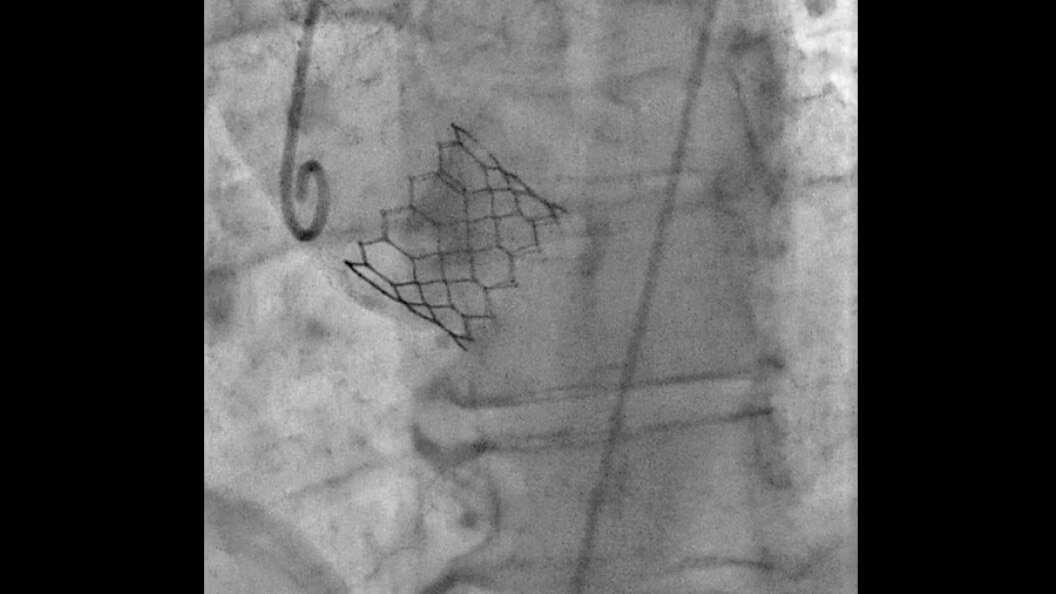

Advanced CBCT for accurate diagnostic and treatment planning

Experience the precision of cone-beam CT, offering high-resolution 3D imaging for accurate diagnostics and treatment planning with enhanced safety and efficiency.